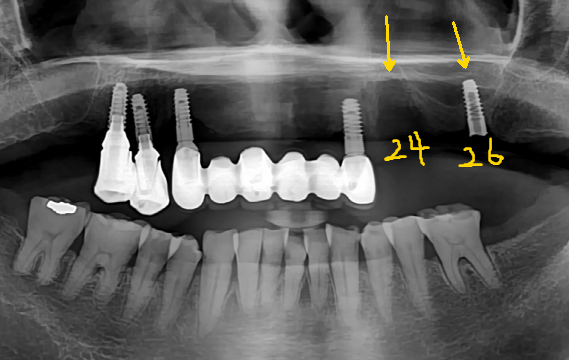

2017년 11월 처음 내원당시 59세의 여성분이신데요

다른 치과에서 3년전에 식립하신 임플란트인데 24번 임플란트는 이미 픽스처(뿌리)가 빠졌고

26번 임플란트는 픽스처(뿌리)가 보철이 탈락되면서 함께 부러져버렸습니다

어찌된 일일까요?

*파란 외곽선이 뼈가 남아 있는 형태이고 노란색 나사모양이 바르게 심어질 임플란트의 식립 계획입니다.

위에 파란 선을 따라가면서 보시는 부분이 치조골(뼈)입니다.

왼쪽 사진 24번 임플란트의 경우 저희가 다시 식립을 하기 위해 계획을 세운 화면입니다.

보시다시피 임플란트를 지지해줄 수 있는 뼈가 거의 없다시피하고

현재 부러진 상태로 남아있는 오른쪽 사진의 26번 임플란트의 경우는 겨우겨우 남아있는 뼈에

식립이 되어있는 상태입니다.

위의 환자분의 경우 픽스처(뿌리)를 잡아줄 수 있는 치조골이 없다보니 임플란트 고정력이 제대로

나오지 않는것은 너무도 당연한 일이고 조금만 관리가 잘못되셔서 염증이 생긴다면 그나마 남아있던

치조골마저 녹아서 없어지니 예후가 안좋을 수 밖에 없습니다.